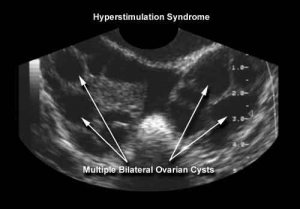

Ovarian Hyper Stimulation Syndrome (OHSS)

All women undergoing ovarian stimulation, such as during an IVF treatment cycle, experience enlargement of their ovaries and a complex change in their hormone balance. The condition is often marked by weight gain, as excess fluid is retained. For this reason it is important to note your weight at the beginning of each IVF cycle.

For up to 5% of stimulated women this can be quite unpleasant with abdominal bloating and pelvic discomfort, however, for <1% of stimulated women, the abdominal pain and fluid retention is so severe that admission to hospital is necessary. Symptoms may include marked abdominal swelling, nausea, vomiting and diarrhoea, lower abdominal pain, and shortness of breath.  Hyperstimulation varies in severity and rarely requires treatment in hospital, but you must contact the clinic if you notice any of the above symptoms so that we can monitor you closely.

"Ovarian Hyperstimulation Syndrome" (OHSS), usually presents a few days after embryo transfer; symptoms being provoked by the hCG injection (Pregnyl/Profasi).